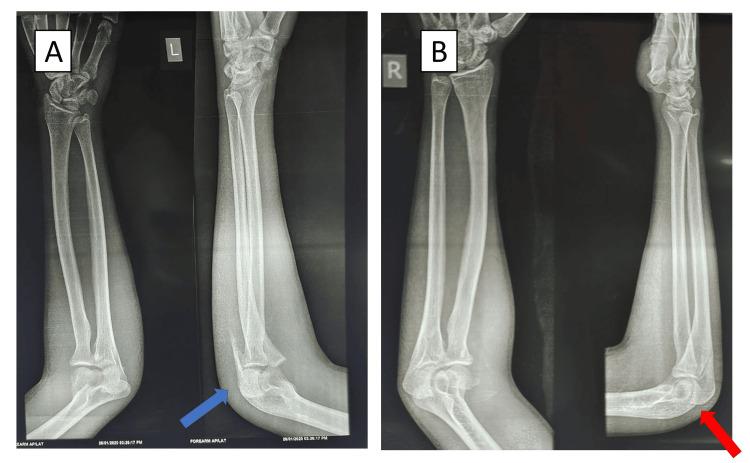

Olecranon fractures are common in orthopedic wards and can be traumatic or pathological in origin. There are very few cases of bilateral olecranon fractures without any associated injuries to the long bones in the literature. We present a unique case of a young 21-year-old male who has an isolated bilateral olecranon fracture following a road traffic accident. The patient had a closed fracture of the ulna on both sides without any associated injuries or neurovascular compromise. Since the patient was young and had good muscle strength preoperatively, we planned fixation of both sides. The patient underwent open reduction and internal fixation with tension band wiring on the right side, which was his dominant side. The left side was operated on by open reduction and internal fixation with an anatomical plate. The patient was started on elbow range of motion on the right side from the secondpostoperative day and started basic activities such as having food independently by the 10th day postoperatively. The physiotherapy was continued in a stepwise manner, and by the sixth week, the patient had a full range of motion on both sides. The patient had resumed his activities of daily living independently by the sixthweek following the surgery. Such cases are rare, and a case-based management plan must be devised for each patient, considering contributing factors such as age, bone quality, osteoporosis, underlying medical comorbidities, functional demands, and muscle strength. We demonstrated a good clinical and radiological outcome by using tension band wiring on the dominant side with a stable olecranon fracture and plating done on the non-dominant side, which had an unstable displaced olecranon fracture.

鹰嘴骨折在骨科病房较为常见,其成因可能是创伤性的或病理性的。文献中极少有双侧鹰嘴骨折且长骨无任何相关损伤的病例。我们报告一例独特病例,一名21岁年轻男性在道路交通事故后发生孤立性双侧鹰嘴骨折。患者双侧尺骨闭合性骨折,无任何相关损伤或神经血管损伤。由于患者年轻且术前肌力良好,我们计划对双侧进行固定。患者右侧(优势侧)接受切开复位张力带钢丝内固定术,左侧采用解剖钢板切开复位内固定术。术后第二天开始右侧肘关节活动度训练,术后第10天开始独立进食等基本活动。物理治疗逐步进行,到第六周时,患者双侧肘关节活动度恢复正常。术后第六周,患者已能独立恢复日常生活活动。此类病例罕见,必须针对每位患者制定基于病例的管理计划,考虑年龄、骨质、骨质疏松、基础疾病、功能需求和肌力等相关因素。我们通过对优势侧稳定的鹰嘴骨折采用张力带钢丝固定,对非优势侧不稳定移位的鹰嘴骨折采用钢板固定,取得了良好的临床和影像学效果。